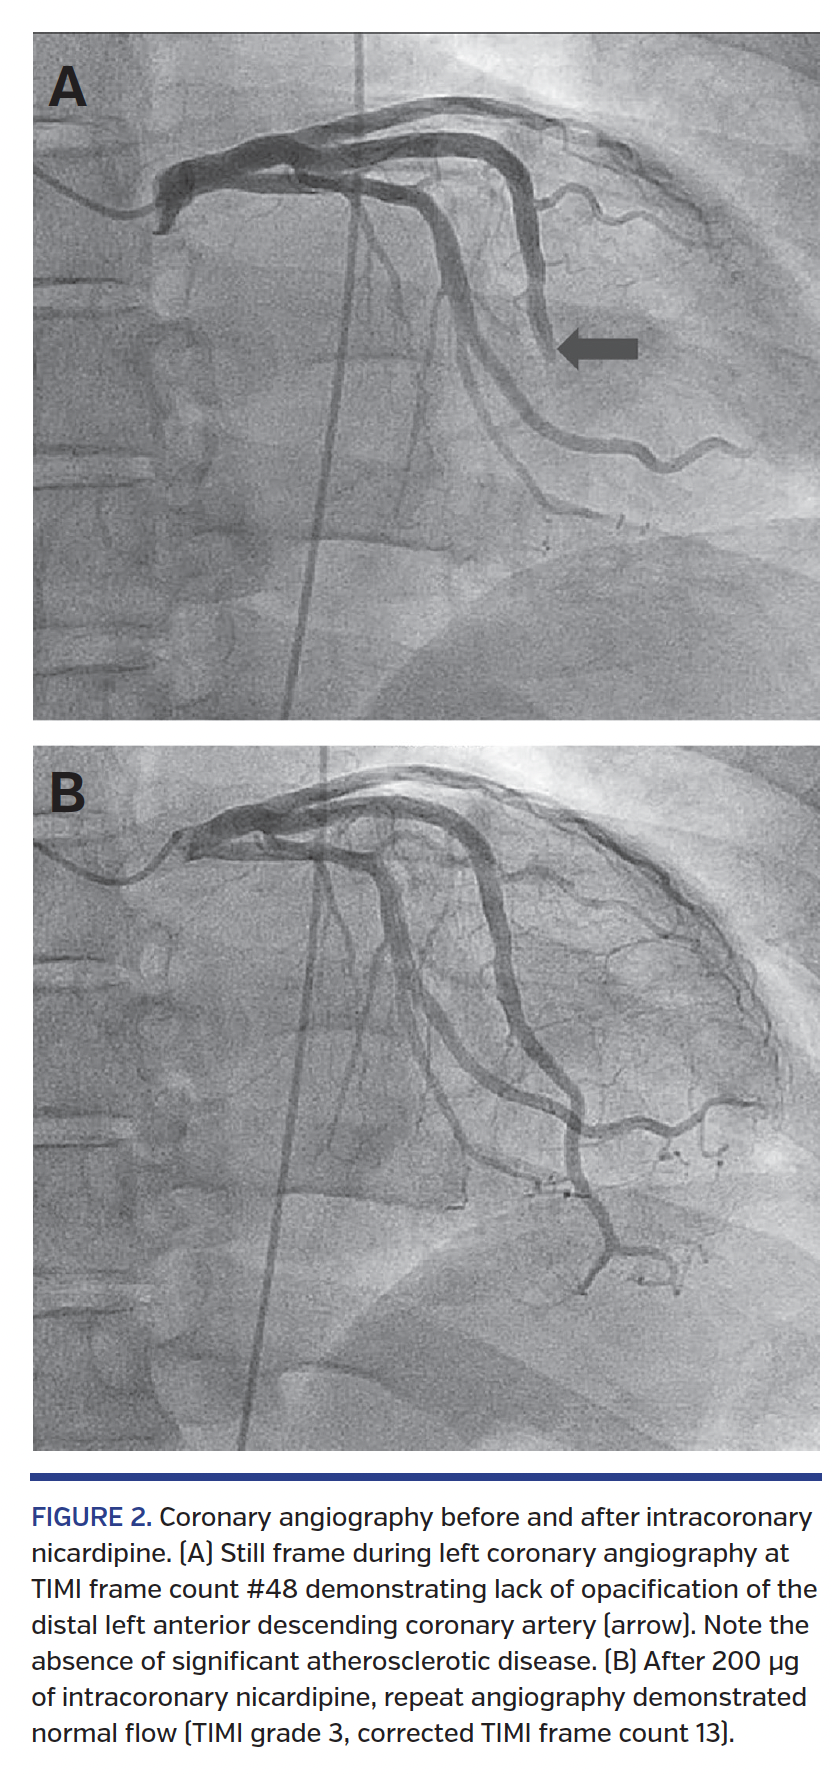

IC nicardipine characteristically resulted in markedly accelerated angiographic filling of the coronary arteries (Figure 2; Video 1); this observation was corroborated by TIMI flow and TFC analysis. In vessels with CSF, TFC improved from 47 ± 17 at baseline to 15 ± 5 after IC nicardipine administration (P<.001) (Figure 3). All vessels demonstrated TIMI 3 flow and TFC <28 following nicardipine. Significant improvement in TFC was seen for all vascular territories (Figure 4). No adverse effects were observed with drug administration.